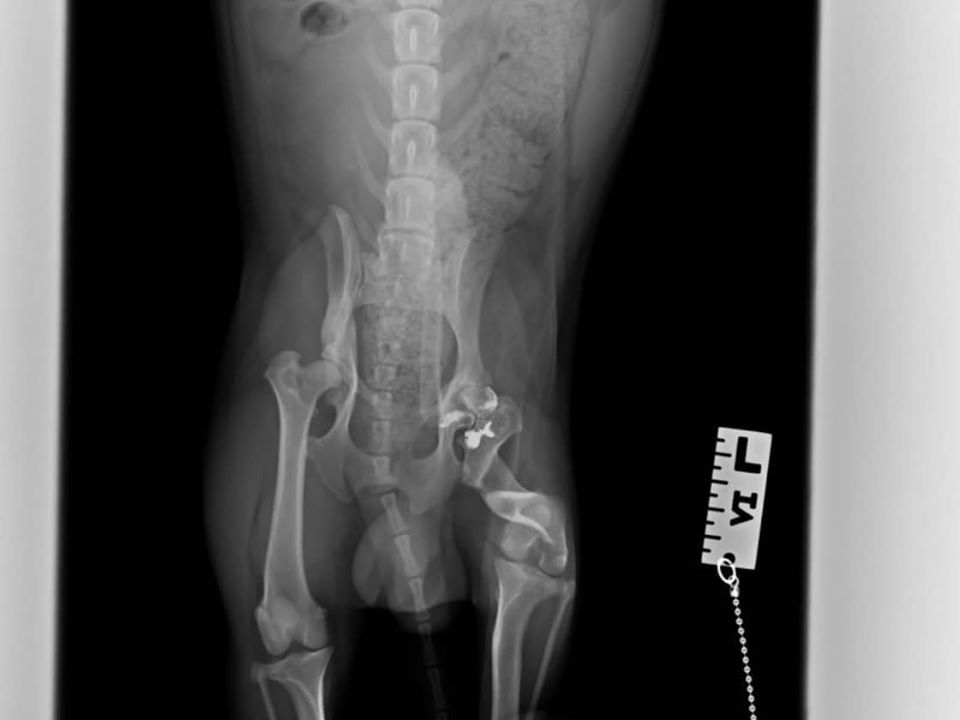

To je Rudi. Rudi je majhen kuža, tehta nekaj več kot 7 kg. Rudi je bil ustreljen (najverjetneje) z malokalibrsko puško 🔫🤐😥.

Diagnoza: hud zlom stegnenice, dislokacija pogačice, omejena gibljivost kolka

Prognoza: 2 operaciji, eno je že prestal, naravnali smo stegnenico, druga ga še čaka – poravnava pogačice, odrstranitev zgornjega dela stegnenice, da se povrne gibljivost kolka in odstranitev metka.